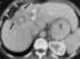

Confluent fibrosis

Retroperitoneal fibrosis or Ormond's disease is a disease featuring the proliferation of fibrous tissue in the retroperitoneum, the compartment of the body containing the kidneys, aorta, renal tract, and various other structures. It may present with lower back pain, kidney failure, hypertension, deep vein thrombosis, and other obstructive symptoms. [Source: Wikipedia ]